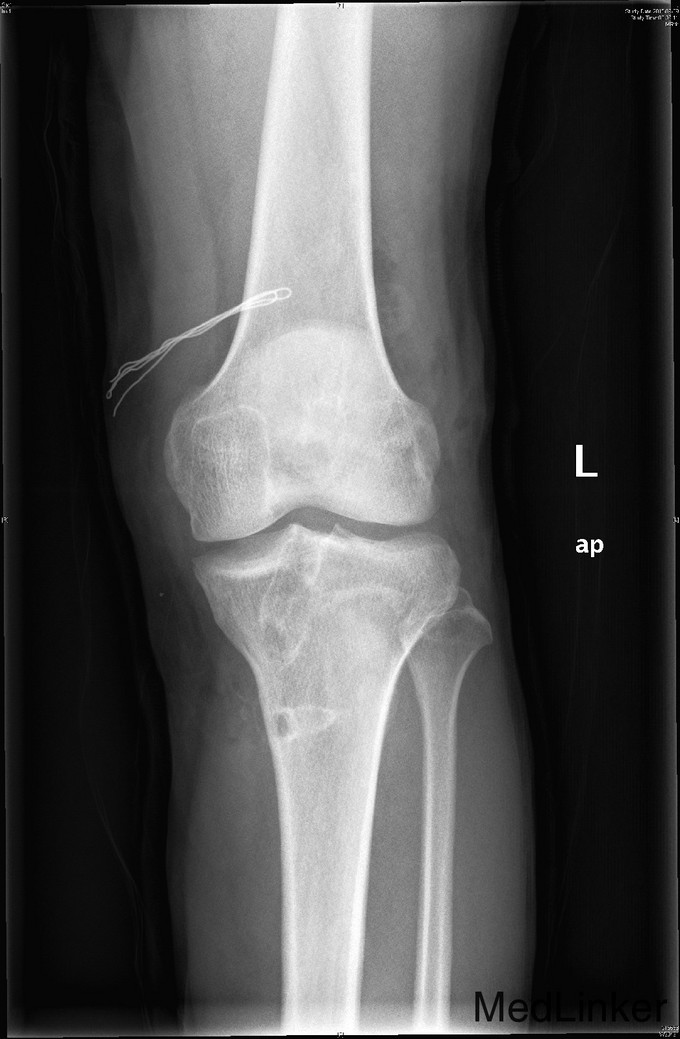

主诉:左膝前交叉韧带重建术后,要求取内固定 。 现病史:患者9年前运动时扭伤左膝关节,后出现左膝不稳、左下肢乏力。患者当时来我院就诊,诊断左膝前交叉韧带损伤,行左膝前交叉韧带自体重建术。患者自觉术后恢复良好,未规律行康复锻炼。2年前患者自觉左膝行走时偶有交锁伴疼痛。今患者为取左下肢内固定物来我院就诊。

查体:右下肢、双上肢肌力及活动度正常。左股四头肌萎缩,肌力V-级。左膝关节无明显肿胀,关节ROM尚正常,关节过伸过屈时无疼痛。髌骨活动度正常,髌周无压痛。浮髌试验(-),压磨髌(-)。麦氏征(+)。关节间隙压痛(+)。ADT(+-),Lachman征(+-),侧方应力实验(-)。双下肢无明显感觉异常。 左膝X线示:左膝术后改变。 注:患者因体内内固定无法进行核磁共振检查,这也是患者强烈要求取出内固定的原因。

诊断:左膝前交叉韧带重建术后,左膝半月板损伤。 治疗:左膝内固定取出术+左膝关节镜下探查+左膝前交叉韧带皱缩+内侧半月板成形术